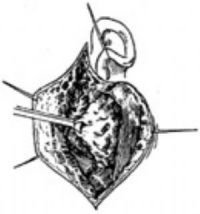

2、分离皮瓣 切开皮肤及皮下组织后即可在腮腺包膜和皮下组织间潜行分离,随之将皮瓣向两侧牵开(图2)。

3、寻找面神经 主要有二种方法,一种是先找出面神经总干,然后分离各分支。另一种是先找出某一分支(如下颌缘支),再找出其他分支,最后找及总干(图3)。可根据肿瘤的位置,大小、移动性等具体情况以及术者的习惯采用不同的方法。暴露面神经总干的方法。面神经离开茎乳孔出颅后,在二腹肌后腹与外耳道软骨所构成的角内向前下方行走。因此可按照乳突为樗,沿外耳道软骨的下缘。向后至乳突前缘,在乳突尖上方及乳突表面下约1cm处可找及面神经总干。

暴露面神经下颌缘支的方法:面神经下颌缘支的位置一般较恒定,它位于咬肌的表面,走向与下颌骨下缘平行。一般约在下颌角上1cm以内。因此寻找时可以下颌角为标志。在腮腺前下缘与咬肌表面相交处细致分离和寻找,神经常与血管伴行,找出分支后,循此逐渐向上找及总干,再在同一平面上找及其他分支。

4、切除腮腺浅叶及肿瘤,将已分离出的腮腺上、下极及前缘连同腮腺导管一起向后方掀起,继续沿神经分支表面向总干分离,最后切继腮腺峡部,此时腮腺浅叶连同位于其内的肿瘤被一并摘除。如肿瘤位于腮腺深叶,亦需摘除浅叶后方能在明视下摘除深叶的肿瘤。